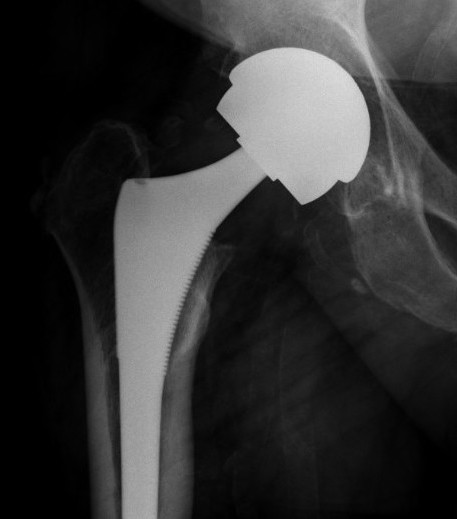

Metal on poly THA Zimmer poly Stryker poly